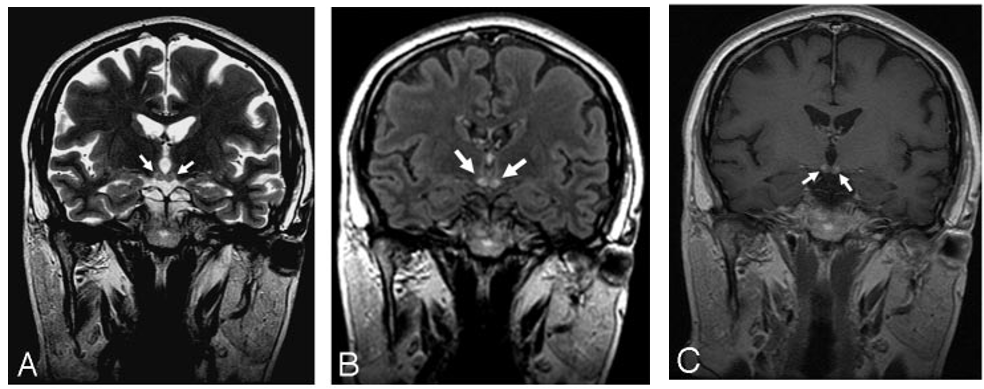

这是由于维生素B1缺乏引起的中枢神经系统代谢性脑病,酗酒是最常见的诱发因素。临床以精神症状、眼肌麻痹和共济失调三主征为主要表现,MRI异常信号围绕第三/第四脑室和导水管。最常受累的结构为乳头体,见于80%的韦尼克脑病患者。如果丘脑背内侧受累,常伴有记忆力障碍。

颅脑MRI冠状位示:双侧乳头体高信号

增强扫描示:双侧乳头体中心强化

颅脑MRI轴位示:双侧乳头体、导水管周围、

穹窿、丘脑背内侧及大脑皮层对称性高信号